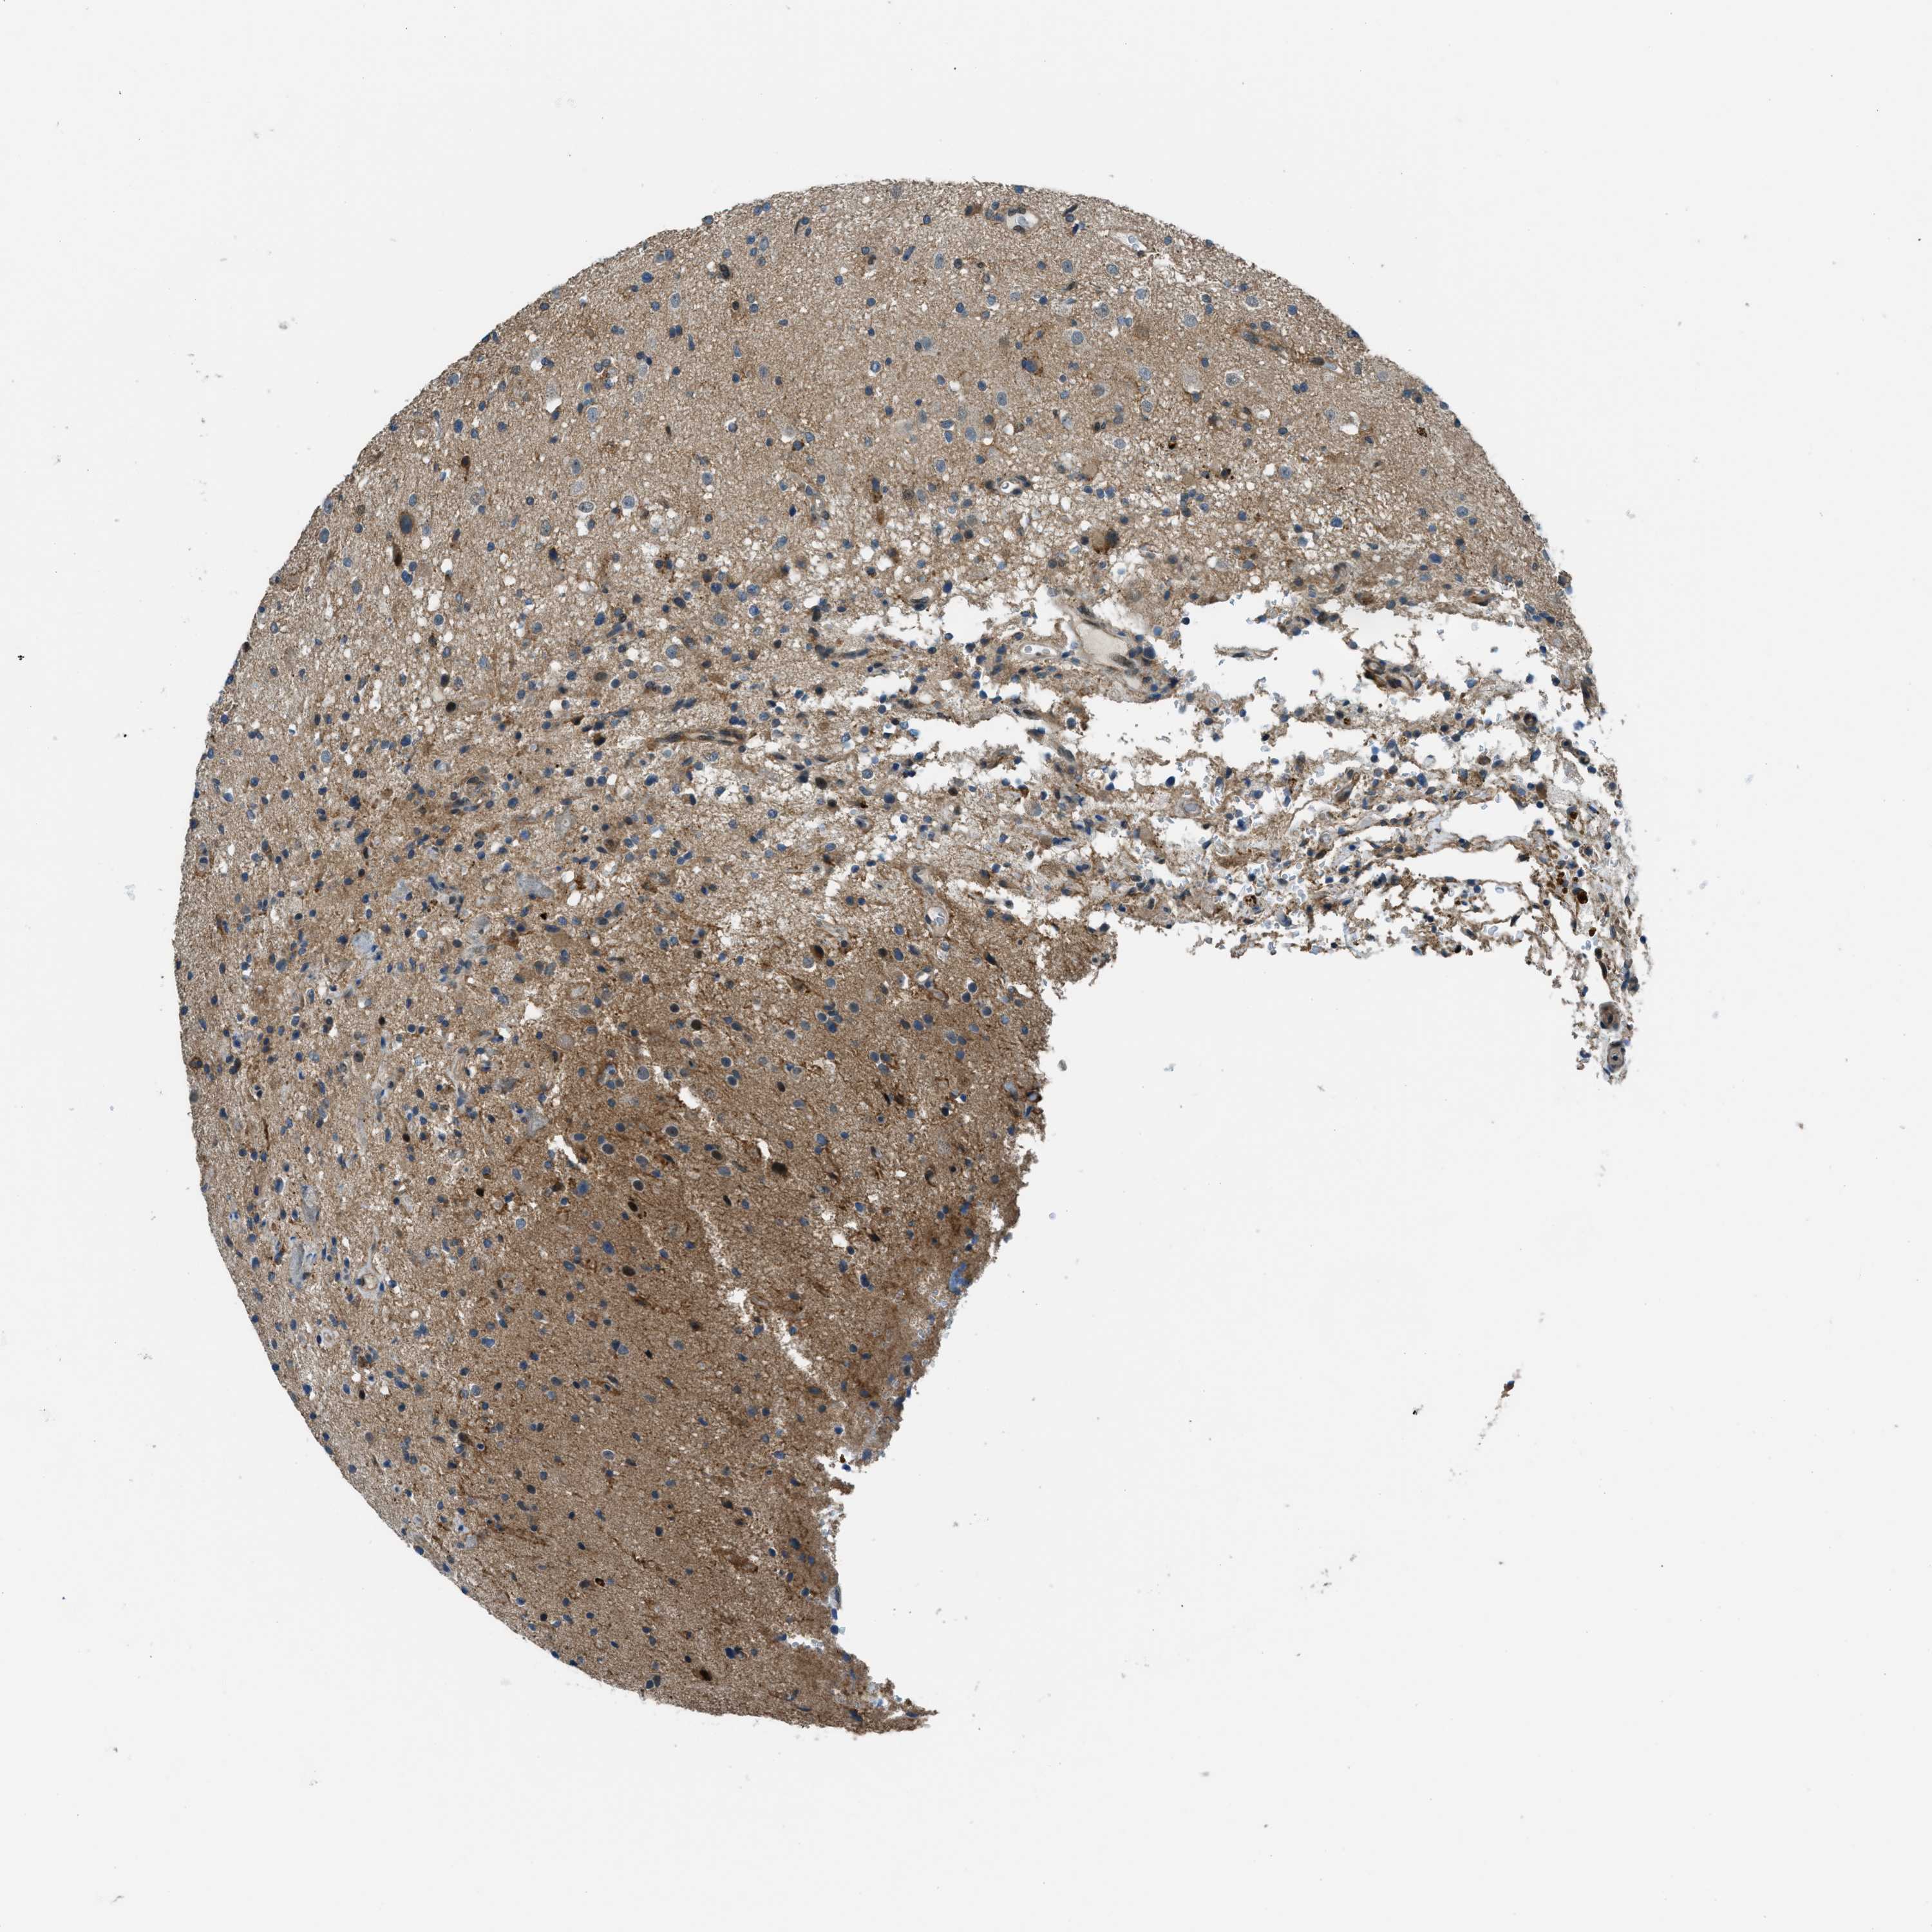

GLIOMA - Protein expressioni

A mouse-over function shows sample information and annotation data. Click on an image to view it in a full screen mode. Samples can be filtered based on level of antibody staining by selecting one or several of the following categories: high, medium, low and not detected. The assay and annotation is described here.

Note that samples used for immunohistochemistry by the Human Protein Atlas do not correspond to samples in the TCGA dataset.

Antibody stainingi

Antibody staining in the annotated cell types in the current human tissue is reported as not detected, low, medium, or high, based on conventional immunohistochemistry profiling in selected tissues. This score is based on the combination of the staining intensity and fraction of stained cells.

Each image is clickable and will lead to virtual microscopy that enables deeper exploration of all samples and also displays staining intensity scores, fraction scores and subcellular localization as well as patient and tissue information for each sample.

Antibody HPA036356

Antibody CAB004986

Antibody CAB017025

Staining

High

Medium

Low

Not detected

Intensity

Strong

Moderate

Weak

Negative

Quantity

>75%

75%-25%

<25%

None

Location

Nuclear

Cytoplasmic/membranous

Cytoplasmic/membranous,nuclear

Glioma, malignant, Low grade

Glioma, malignant, High grade

Glioma, malignant, NOS